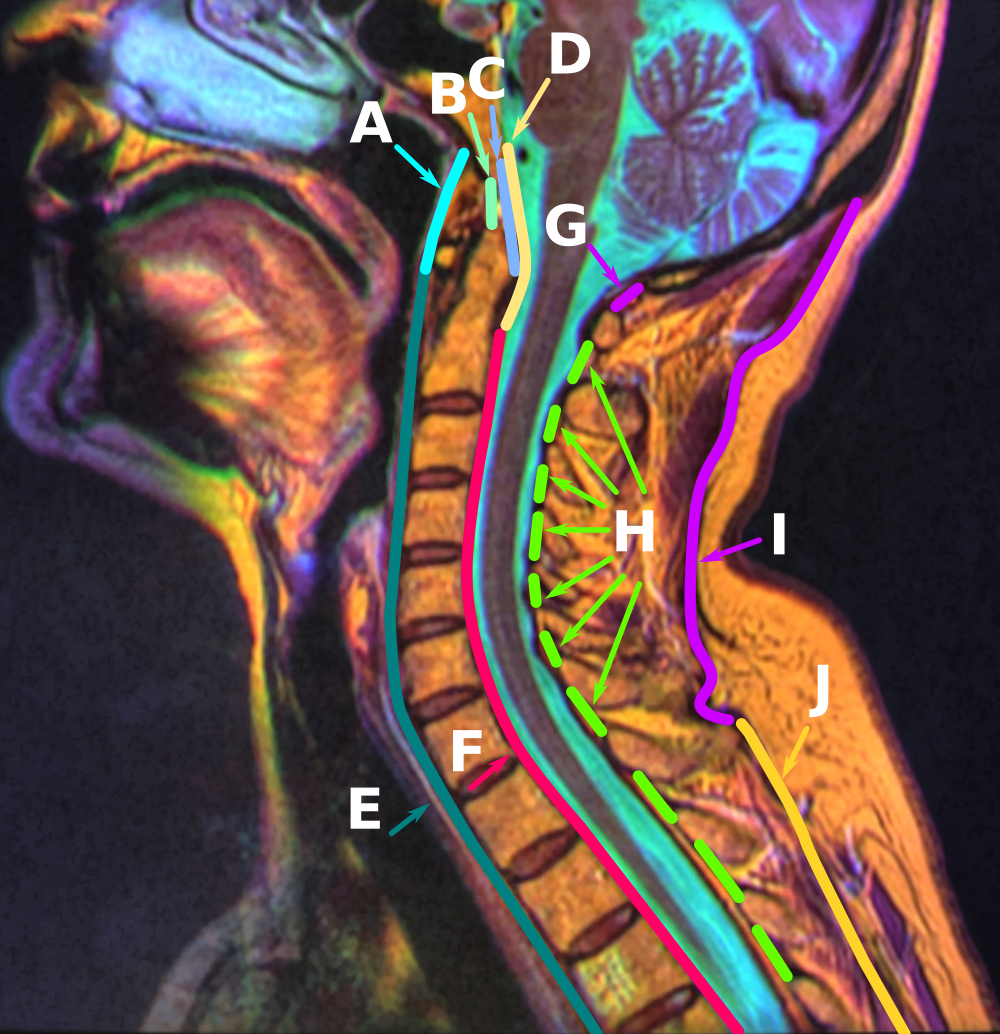

척추와 관련된 인대 - 세로인대(전방종인대, 후방종인대), 황색인대, 극상인대

척추의 앞쪽(전방면)을 따라서 내려가는 인대입니다. 복부의 모든 척추와 추간판을 따라서 내려갑니다(위 그림에서 E)

척추의 뒤쪽면(후방면)을 연결하는 인대입니다. 척주가 심하게 굴곡하는것과 후방 척추 추간판 탈출증을 방지합니다(위 그림에서 F)

황색인대는 인접한 척추의 얇은 판(laminae)을 연결하는 황색의 탄력석 인대입니다(위그림에서 H)

일곱 번째 경추에서 천골까지 척추를 따라가는 인대입니다(위 그림에서 J)

극상인대와 연속적인 목 후방면의 인대입니다(위 그림에서 I)